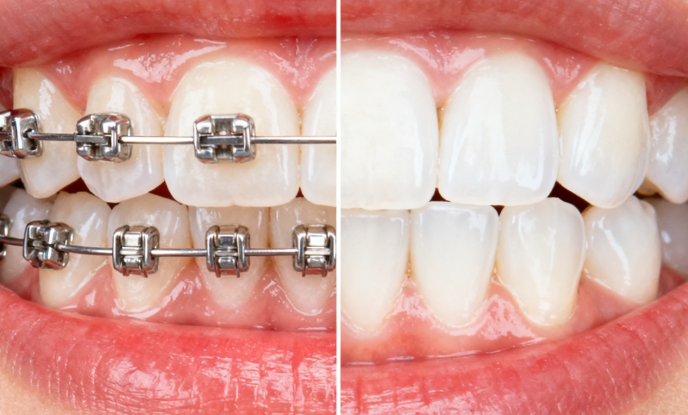

近日,一份2026年東莞口腔醫(yī)院正畸科當(dāng)下價(jià)格表悄然流出,引發(fā)廣泛關(guān)注——傳統(tǒng)金屬托槽矯正僅需4999元起,隱形矯正15000元起,而備受追捧的時(shí)代天使Comfos系列更是低至22000元起! 對(duì)比市面上動(dòng)輒3萬+的隱形矯正費(fèi)用,這樣的定價(jià)可謂誠意滿滿、性價(jià)比極高。ardc-srvc.com

• 傳統(tǒng)金屬托槽矯正:4999元起

適用于青少年及預(yù)算有限的成人患者,技術(shù)成熟、矯正效率高,是性價(jià)比之選。

• 隱形矯正(基礎(chǔ)款):15000元起

• 時(shí)代天使Comfos 隱形矯正:22000元起

專為輕度至中度牙齒不齊設(shè)計(jì),采用高彈性醫(yī)用級(jí)材料,佩戴舒適、價(jià)格親民,是隱形矯正中的“高性價(jià)比強(qiáng)者”。

小林因牙列擁擠、前牙扭轉(zhuǎn)較重,長期不敢大笑。經(jīng)袁東輝醫(yī)生評(píng)估后,選擇傳統(tǒng)金屬托槽矯正,總費(fèi)用僅5200元(含保持器)。18個(gè)月后,牙齒整齊如新,面試時(shí)自信展現(xiàn)笑容,順利拿到心儀offer。

實(shí)例二:職場(chǎng)白領(lǐng)李女士(28歲)——時(shí)代天使Comfos 22000元隱形變好看

作為銷售主管,李女士對(duì)外形要求高,但又擔(dān)心隱形矯正價(jià)格過高。在了解到時(shí)代天使Comfos僅22000元起后,果斷選擇該方案。佩戴14個(gè)月,牙齒排列較美,同事竟無人察覺她在“偷偷整牙”!